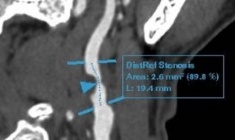

Ca can thiệp được tiến hành trong khoảng 2 giờ với sự phối hợp nhịp nhàng của ê-kíp chuyên môn giàu kinh nghiệm. Dưới sự hỗ trợ của hệ thống chụp mạch số hóa xóa nền (DSA) hiện đại, các bác sĩ đã mở đường vào mạch máu, đưa dây điện cực đến vị trí thích hợp trong tim để điều chỉnh hoạt động hai buồng thất. Quá trình thao tác được giám sát liên tục trên màn hình DSA, đảm bảo độ chính xác tuyệt đối.